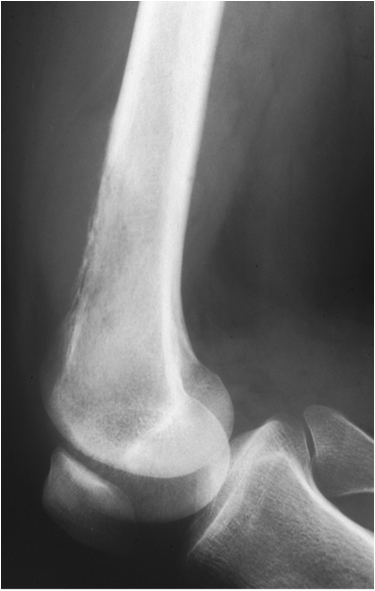

Primary osteoarthritis involves weight bearing joints such as the knee, where changes are seen especially in the medial compartment and the patellofemoral compartment. In the hip changes are seen superolaterally. The tibiotalar joint is rarely significantly involved, except for changes along the anterior margin of the distal articular surface of the tibia. These are most likely posttraumatic in origin.

Fig. 13. A) Knee joint with degenerative changes. Note the sclerotic medial tibial plateau and joint space narrowing. A small osteophyte is seen on the medial femoral condyle. B.) Pelvis with marked degeneration of both hip joints. The right femoral head shows lateral osteophyte formation and is deformed. The joint space is narrow with increased subchondral sclerosis of the acetabular roof. The left hip has a marked joint space narrowing and lateral osteophyte formation. The femoral head shows increased density due to sclerotic areas and irregularity.